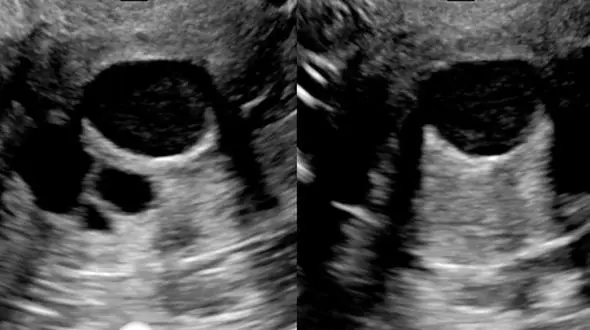

رکنا: کیست های تخمدانی معمولا خوش خیم هستند و اغلب بدون علامت و بدون نیاز به درمان از بین می روند اما در برخی موارد، کیست های تخمدانی ممکن است باعث ایجاد درد، مشکلات هورمونی و حتی نازایی شوند.